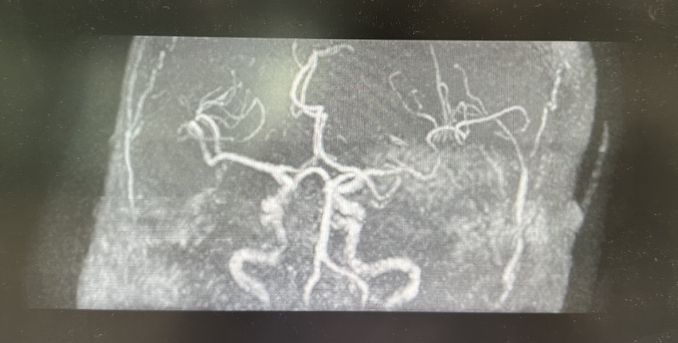

图一:支架植入术前